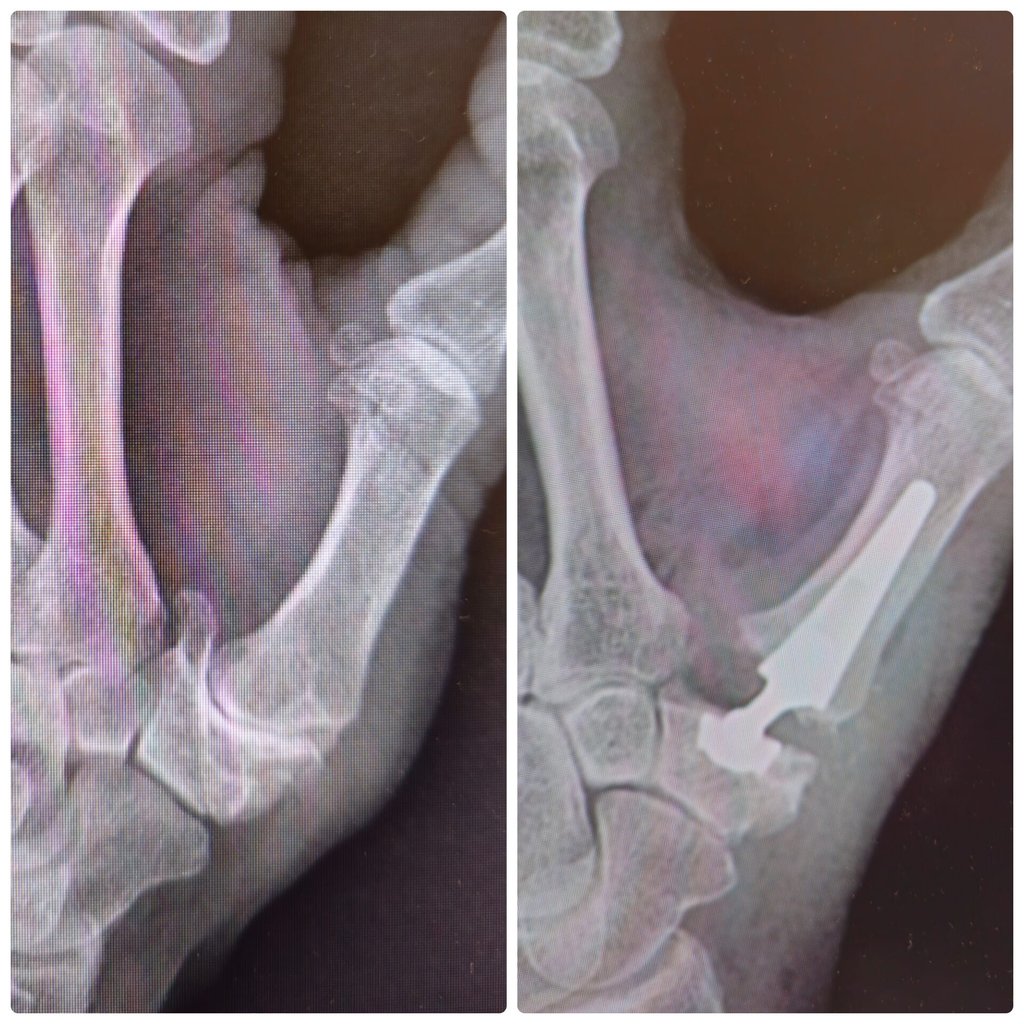

Articulación muy susceptible a algunas enfermedades como la artrosis, las fracturas de radio y cubito o las lesiones de los ligamentos.

Proyectos Médicos

Avances en cirugía de mano y muñeca para mejorar vidas.